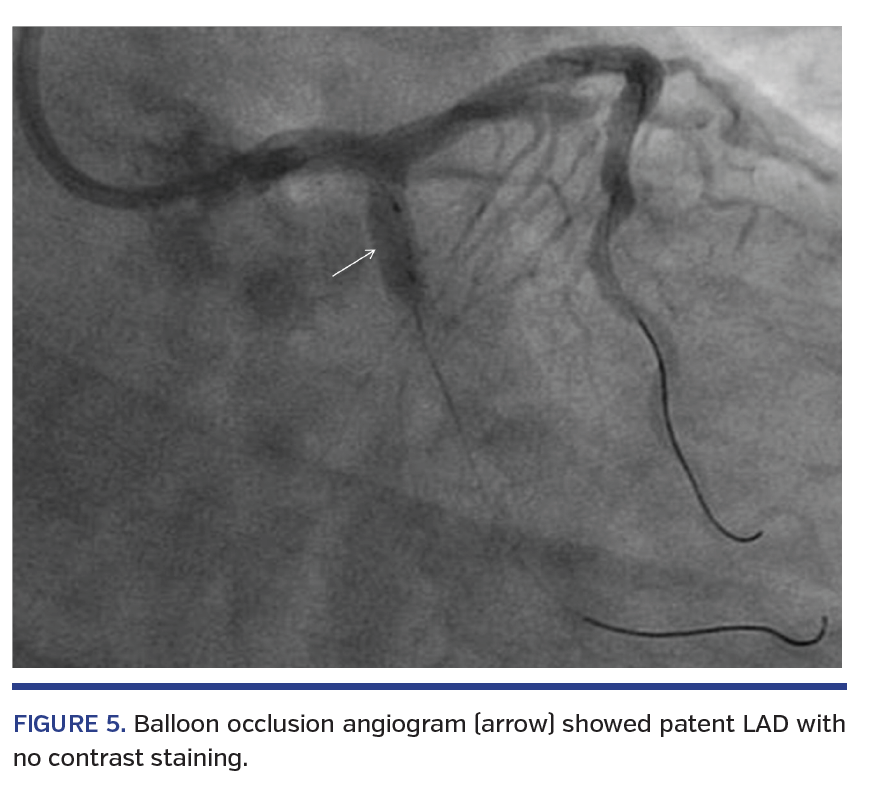

Angiography after OCT acquisition showed hydraulic spiral dissection from the proximal LCX extending retrograde into the proximal LAD and distal left main (LM) stem (Figures 3 and 4; Video 2). A 4.0 mm semicompliant (SC) balloon was immediately inflated at the LCX dissection site for 1 minute. Subsequent angiogram with balloon occlusion of the LCX showed patent LAD with no contrast staining (Figure 5). A 4 x 24 mm DES was implanted from the LM into the LCX, overlapping the initial LCX stent. The final angiogram was satisfactory and the patient remained stable throughout the procedure.